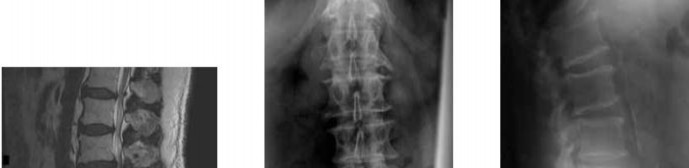

Question 8

A 42-year-old man presents with 6 weeks of right leg pain radiating down the lateral aspect of his calf to the dorsum of his foot. He has a 3/5 weakness in extensor hallucis longus (EHL). He has failed conservative therapy. Which nerve root is most likely compressed?

Explanation